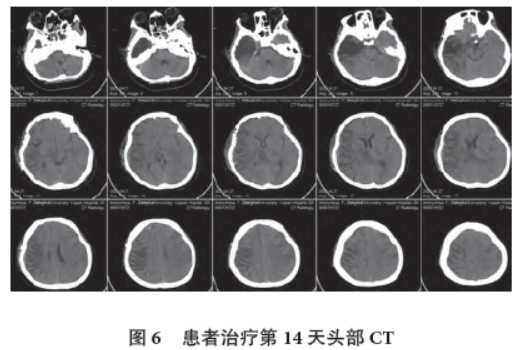

治疗第14 天,可遵嘱闭眼,脑电图左侧半球2~3 Hz 混合活动,前头部著,双侧后头部、中线区低波幅12~14 Hz β 活动,右侧半球电活动较左侧半球减弱(图5),头部CT 提示脑水肿较前减轻,右侧半球白质密度沿脑沟走形增高(图6)。